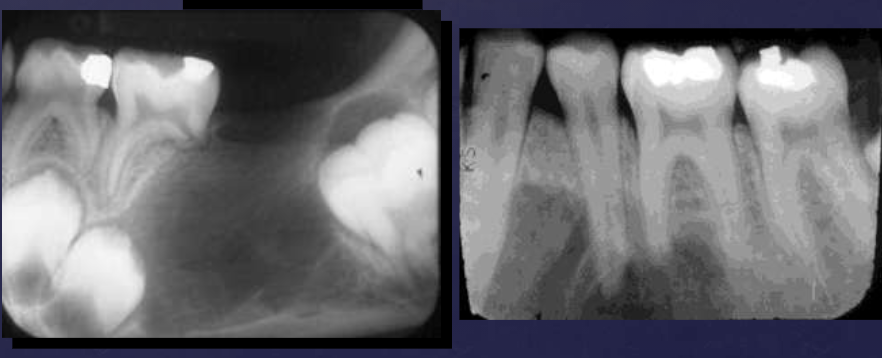

radiographic features of cherubism

bilateral multilocular radiolucencies

multicystic appearance

expansion/thinning of cortices

uncommon perforation

tooth displacement, resorption

radiographic features of central giant cell granulomas (CGCG)

well defined periphery, not corticated generally

radiolucent: small lesions

internally: subtle granular calcifications, thin wispy septae

if adjacent to teeth: absence of lamina dura